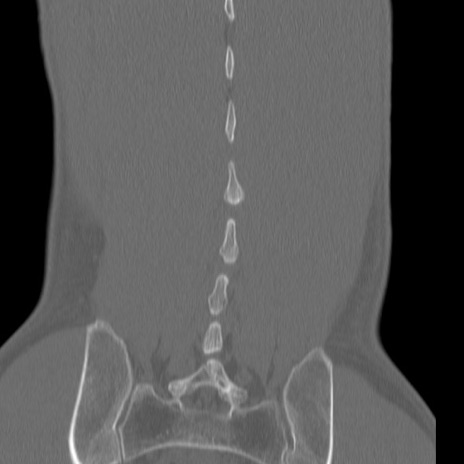

症例3 腰椎CT(冠状断像)

腰椎CT

3D再構成